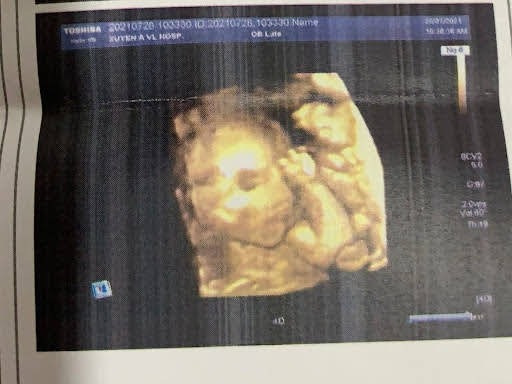

Nay em đi gặp gái yêu của em đây các bác ạ..con đc 21 tuần rồi trộm vía cưng lắm.. mỗi lần mẹ thai giáo là máy mẹ nhìu🥰con còn chào bs siêu âm cho con nữa nè..mẹ con lên 1 cân thôi..ăn bao nhiu đều vào con hết..nay 21 tuần mà con nặng 420gam rồi..bs khen con ngoan lắm nè 🥰mẹ con chúc các mom có 1 thai kỳ mạnh khoẻ nhé